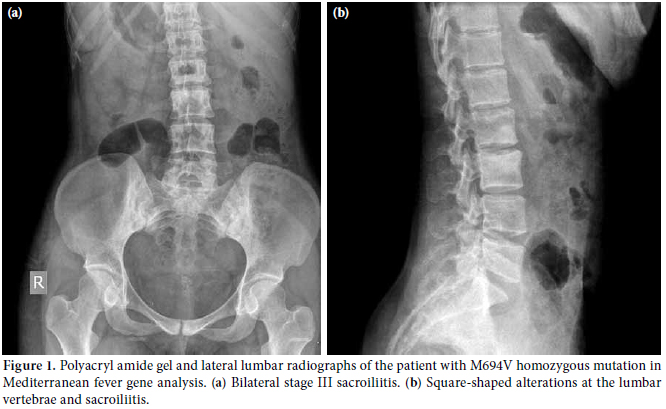

The mean age are onset of arthritis/spondylitis for the study participants was 20.4±9.1 years. Seven patients had a family history of FMF. In 13 patients (44.8%), fever coincided with arthritis/spondylitis; however, peritonitis coincided with arthritis/spondylitis in 20 (69%) patients, and pleuritis in six others (20.7%). Their medical history indicated that four patients had undergone total hip replacements, one patient had had a knee debridement, and one had undergone an appendectomy. Arthritis was observed in 24 of the patients, with 15 having monoarthritis and nine having oligoarthritis. The ankle joint was the most affected joint (n=13). This was followed by the knee (n=9), hip and small joints of the hands (n=5), and small joints of the feet (n=4) (Table 1). Five patients had both arthritis and spondylitis while five others had only spondylitis. The information regarding the patients with spondylitis is summarized in Table 2, and the radiographs of the patients with spondylitis are shown in Figure 1. An analysis of the MEFV gene was performed on 27 patients, and the M696V mutation was the one that was most frequently seen (Table 3). All patients with a history of total hip replacement had the M694V homozygous mutation (Figure 2). Additionally, an analysis of the HLA-B27 gene was conducted on 21 patients, and two tested positive. Because the patients with spondylitis fulfilled the criteria for FMF and ankylosing spondylitis (AS), we regarded them as having both. One of these patients had spondylitis while another had only ankle arthralgia and arthritis which was localized in the toe. Almost all of the patients had colchicine therapy, but they were also administered different medications such as nonsteroidal anti-inflammatory drugs (NSAIDs), disease-modifying antirheumatic drugs (DMARDs), and anti-tumor necrosis factor (anti-TNF) agents according to the presence of either peripheral arthritis or spondylitis (Table 4). In reviewing the medical records of the patients, two had amyloidosis proven by a renal biopsy. The others had normal renal function tests.

Spondylitis is one of the musculoskeletal involvements of FMF. Kaşifoğlu et al.[12] reported that 7% of FMF patients had sacroiliitis. However, when patients with only musculoskeletal complaints were added to the analysis, 32.7% of them had this inflammatory condition. Different imaging methods for sacroiliitis have provided different results in the literature.[23,24] It is a general consensus that spondyloarthropathy in FMF cases is negative for HLA-B27 and that spinal ankylosis is also absent.[5] Patients who are positive for HLA-B27 and who have spinal ankylosis are considered to have FMF that coincides with AS.[25,26] We found that 34.5% of our cases had spondylitis, but only one of these patients tested positive for HLA-B27. Therefore, this patient was considered to have both FMF and AS. We found that the most common mutation in these patients was M694V. Similarly, Kaşifoğlu et al.[12] reported that the M694V mutation was more common than other mutations.